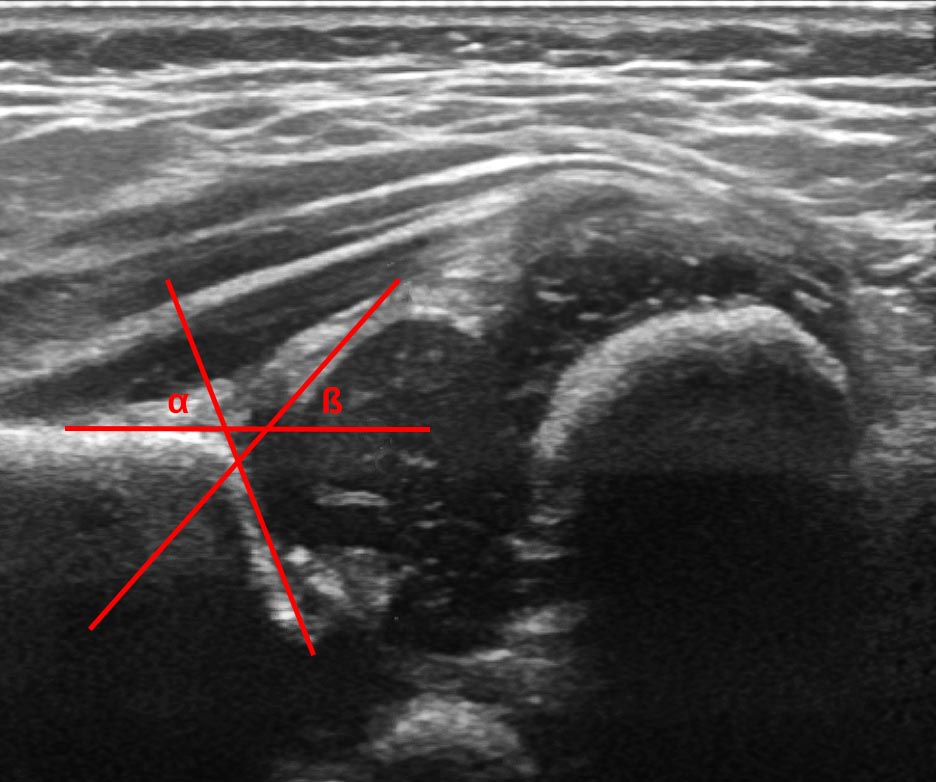

To measure the angle, a baseline plane is drawn along horizontal or vertical ilium starting at the point the perichondrium meets the ilium. A further line is drawn through points placed at the lower limb of the ilium and at the turning point. just touching the bone, not cutting in to it. The angle between baseline and this line is the alpha angle. The angle from the baseline to a line through the turning point and the middle of the labrum is the beta angle. The lines should not cross at a single point.

• Graf I: normal hip (alpha >=60°), with (Ib) or without (Ia) a beta angle >55°

• Graf IIa: immature hip (alpha 50-59°) less than 12 weeks of age, and at 6 weeks+ either maturing appropriately (+) or inappropriately (-) for age

• Graf IIb: dysplastic hip, (alpha 50-59°) >13 weeks age

• Graf IIc: severely dysplastic hip (alpha 43-49°, beta <77°)

• Graf D: decentred hip (alpha 43-49°, beta >77°)

• Graf III: dislocated hip (alpha <43°), the perichondrium passes upwards

• Graf IV: severely dislocated hip (alpha <43°), the perichondrium passes horizontally or downwards